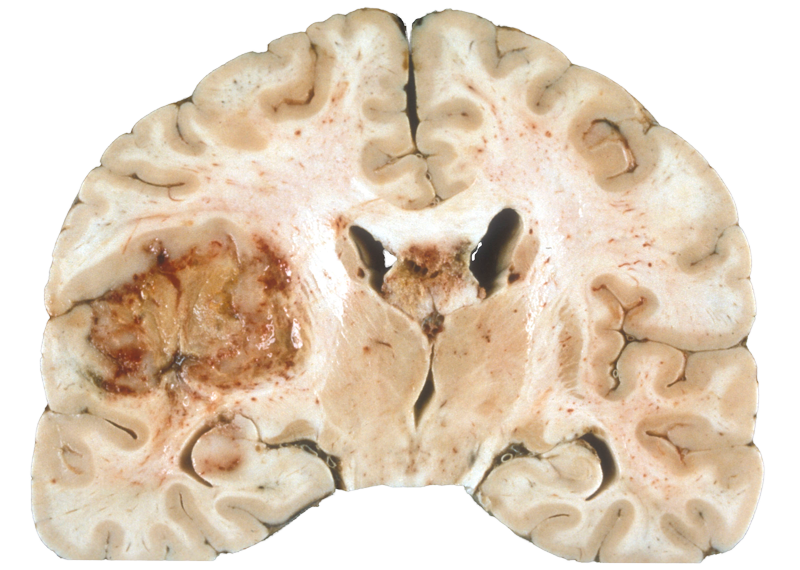

Dr. Michael Lim is a Professor of Neurosurgery, Oncology, Otolaryngology, and Radiation Oncology at Johns Hopkins. Dr. Lim obtained his MD from the Johns Hopkins University School of Medicine. He then completed his residency in Neurosurgery at Stanford University Hospital. Dr. Lim’s surgical interest is in both benign and malignant brain tumors, with a particular interest in gliomas (including ependymoma), meningioma, pituitary tumors and skull base tumors. He has extensive experience in new and innovative neurosurgical techniques including image guided surgery, microsurgery, minimally invasive procedures and endoscopic surgery. Dr. Lim is also the Director of the Brain Tumor Immunotherapy Program at Johns Hopkins. His primary research interest is developing immune-based therapies against brain tumors. His research laboratory is focused on understanding the mechanisms of immune evasion by primary brain tumors. Findings from Dr. Lim’s laboratory are directed towards translation to novel therapies against brain tumors. In addition to running a laboratory, he also directs the immunotherapy clinical trials program at Johns Hopkins. Dr. Lim currently serves as the principal investigator of several large brain tumor immunotherapy clinical trials based on findings from his laboratory.

Dr. Waziri is currently CEO and Co-Founder of iCE Neurosystems, a privately held medical device company. He was previously Director of the Brain Tumor Program at the Inova Neuroscience Institute. Prior to taking the position at Inova he was Assistant Professor of Neurological Surgery and faculty in the Cancer Biology program at the University of Colorado. His research has focused on the study of mechanisms involved with the suppression of cellular immunity by myeloid-lineage cells in human glioblastoma, identified through the analysis of fresh human tissues. Dr. Waziri has served as Principal Investigator for a range of early- to late-phase clinical trials in primary and secondary glioblastoma, including several investigator-initiated first-in-human pilot studies encompassing serial immunomonitoring in patients to explore restitution of cellular immune function by targeting myeloid-derived immunosuppression.

Dr. Wen is Professor of Neurology at Harvard Medical School, Director of the Center For Neuro-Oncology at Dana-Farber Cancer Institute, Co-PI of the Adult Brain Tumor Consortium, Steering Committee Member of the Response Assessment in Neuro-Oncology (RANO) Working Group, and President of the Society of Neuro-Oncology. He was previously the Editor-In-Chief of Neuro-Oncology. His research is focused on novel treatments of brain tumors and optimizing clinical trial design, endpoints, and response assessment.